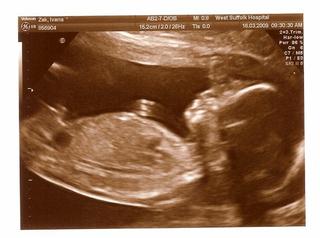

Ahojte,chcem Vas poprosit,kedze vacsina z Vas uz ma aj deti aj skusenost,ked ste zistovali pohlavie,ako vyzerala mala cikulka? My sme videli taky maly hrbolcek tam a dokt.povedala,ze je to girl a ma tam (neviem co neporozumela som) little hampf sa to vyslovilo a neviem najst vyraz,ktory to ma byt ☹

@mikailla urcite to dr. na uzv s rokmi praxe vie odhadnut lepsie ako rodic amater 😀 ale nikdy to nie je stopercentne samozrejme... hoci v dnesnej dobe sa uz malo mylia... ja som ani UZV nepotrebovala, v oboch pripadoch som akosi podvedome vedela co cakam 😀

@mihouk - jeziiiis dakujeeem ANOO asi to bude to slovicko co hladam cely den,hrbolcek 😀 😀 ja uz som skusala aj vybezok,veklenok,hoco a toto ma ani nenapadlo 😀 Dakujem aj za foto,tak takto to nevyzeralo,hi 😅 ,tak im asi budem verit. @newyorkgirl - No to som aj ja povedala,ze asi blba nie je,ze vie co hovori,ale na SR mi povedali,ze bude chlapcek a ked sme videli ten hrbolcek taky malinky tak sme hned,ze naozaj a ona povedala girl 😅 tak sok 😀 DAKUJEM VAM KRAASNE !!!!! zelam dobru nocku 😵